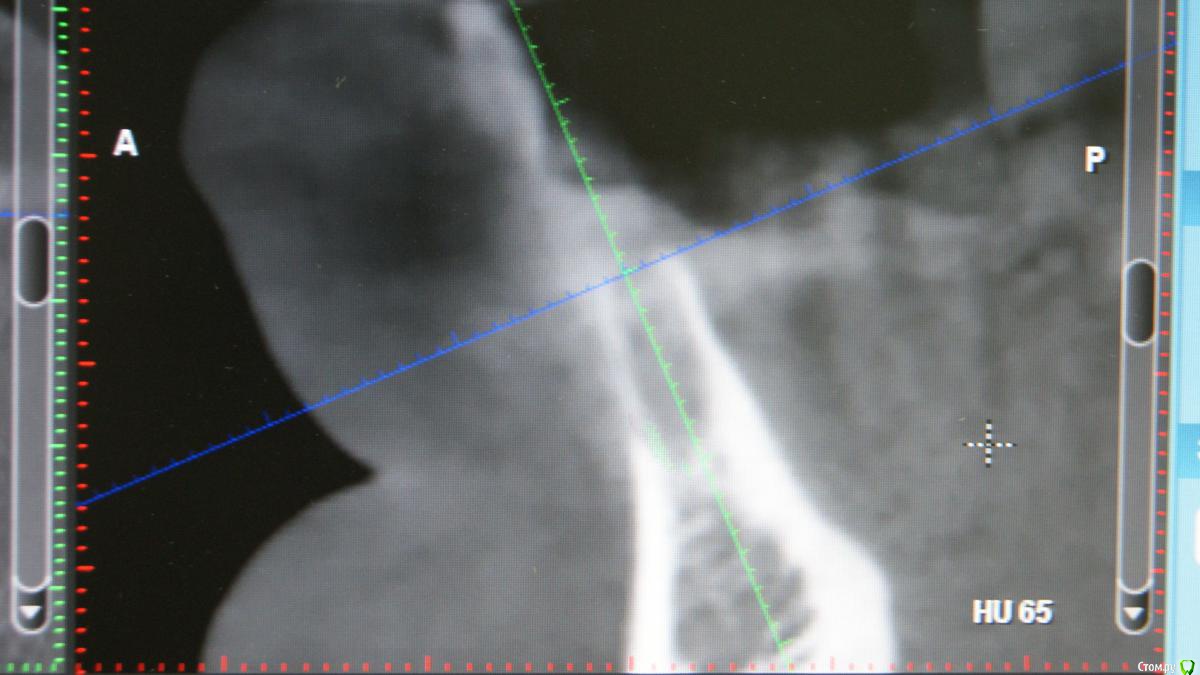

Jurai Опубликовано 26 декабря, 2016 Автор Поделиться Опубликовано 26 декабря, 2016 Как вообще впечатления от Адина?Я скажу откровенно - двойственные впечатления. Да, непафосно, да, просто, да, бывают резорбции по шейке. Но за три года, что я с ними работаю, в минусе два, ставлю почти исключительно Swell. Один вывернулся при вот такой картине Второй убрала при такой, трепаном еле выпилила, полчаса возиласьЕдинственное, я их ставлю только там, где можно хоть саморез по гипсокартону ввернуть и он интегрируется, то бишь, в идеальные условия. Ссылка на комментарий